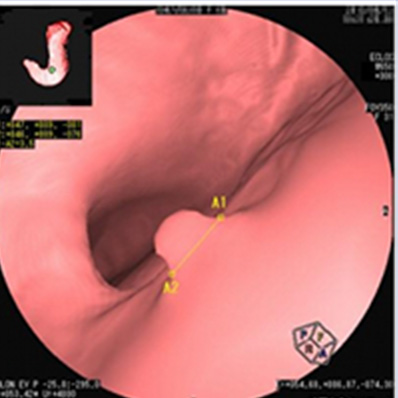

早期胃癌

内視鏡で発見しました。